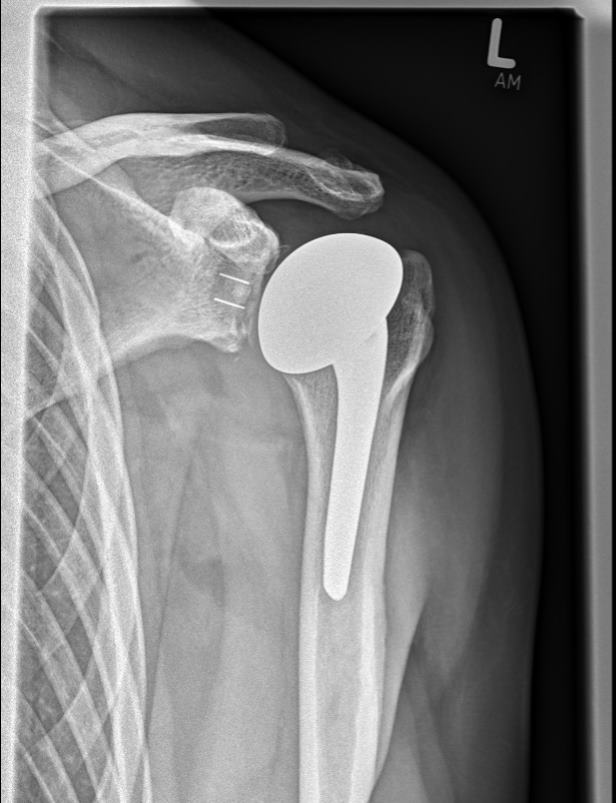

Einen weiteren Schwerpunkt in der Traumabehandlung stellt die Versorgung von Schulterbrüchen dar.

Während bei jüngeren Patienten die Rekonstruktion von Knochen und Gelenken im Vordergrund steht, führt bei älteren Patienten häufig der Gelenkersatz zur schnelleren Wiederherstellung der Beweglichkeit.

Hierfür kann die umfangreiche Erfahrung der orthopädischen Klinik in der Schulterendoprothetik angewandt werden. Dazu werden die Art der Endoprothese und die Einsatzmöglichkeit individuell geplant und umgesetzt.